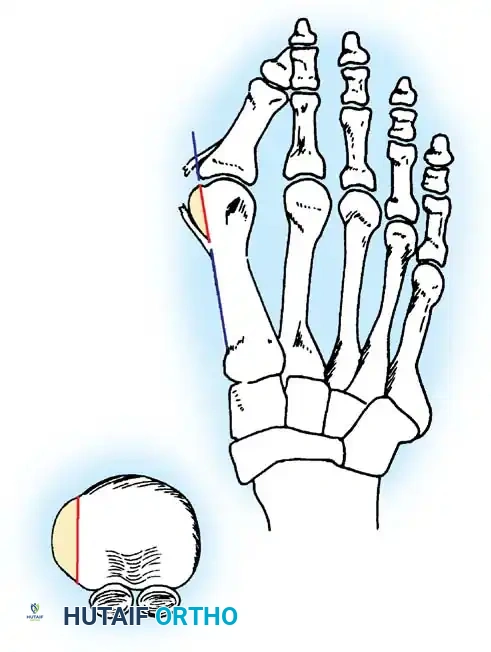

Two other anatomical variants involving the articular surface of the fi rst metatarsophalangeal joint can lead to hallux valgus. In the fi rst variant, the articular surface of the metatarsal head is offset, resembling a scoop of ice cream sitting at an angle on a cone (Fig. 78-6). This has been described as the distal metatarsal articular angle (see Fig. 78-8). In the second, the articular angle of the base of the proximal phalanx in relation to its longitudinal axis is offset. This has been described as the phalangeal articular angle. Although the normal range of these angles is generally considered to be 7 to 10 degrees for the phalangeal articular angle and 10 to 15 degrees for the distal metatarsal articular angle, exact measurements are diffi cult to reproduce because of the variability of radiographic and measurement techniques. Increasing evidence indicates, however, that the failure to correct these two deformities, especially the distal metatarsal articular angle, can cause unsatisfactory results after surgery in some patients. Forceful straightening of the hallux should be avoided if it sacrifi ces tarsalgia. The entire forefoot must be evaluated for these multiple components of hallux valgus before surgical planning is complete and recommendations can be made to the patient. The controversy continues over which deformity is the essential lesion in hallux valgus: metatarsus primus varus or lateral deviation of the great toe. Each is incriminated as the cause of the other. The strongest data probably support lateral deviation of the great toe as the primary deformity in most patients, followed by medial angulation of the fi rst metatarsal, but metatarsus primus varus may be the principal cause in adolescents. Further controversy surrounds the role of footwear as the prime offender in the development of hallux valgus. Most orthopaedic surgeons have seen unilateral hallux valgus when both feet are clinically and radiographically the same structurally except that one foot has a bunion deformity and the other foot is normal. Evidence supports that hallux valgus may be familial, especially when it occurs in adolescents. Although no study of shod and unshod societies has implicated inappropriate footwear as the sole cause of hallux valgus, after genetic factors, binding, unphysiologically designed footwear probably is the major cause in modern societies. Hypermobility of the fi rst ray also has been suggested as a causative factor in the development of hallux valgus and fi rst metatarsal varus, but this is controversial. Coughlin and Shurnas, Myerson and Badekas, King and Toolan, and Faber et al. offer excellent discussions of this problematic area. Finally, certain anatomical and structural abnormalities almost certainly play a causative role in hallux valgus. Pronated fl atfeet, abnormal insertion of the posterior tibial tendon, increased obliquity of the fi rst metatarsomedialcuneiform joint, an abnormally long fi rst ray, incongruous articular surfaces of the fi rst metatarsophalangeal joint, and excessive valgus tilt of the articular surface of the fi rst metatarsal head and proximal phalangeal articular surface may contribute singly or in combination to the deformity and infl uence the recommended treatment. Hypertrophy of the medial eminence has been described as a component of hallux valgus deformity since the earliest reports; however, more recent investigations, including those of Thordarson and Krewer, have found that bony proliferation is not a component of the pathoanatomy of hallux valgus and that the prominence of the medial eminence results from the combination of metatarsus primus varus and medial deviation that uncovers the articular surface. Thordarson and Krewer compared radiographs of 50 feet in patients who had surgery for hallux valgus deformity with radiographs of 50 feet from a control group without hallux valgus deformity and found little difference in the average width of the medial eminence (4.4 mm and 4.1 mm). With more than 130 operations recommended for the treatment of hallux valgus, it is practical to describe only

Inadequate vascularity or sensibility should be investigated thoroughly before bunion surgery is considered. In addition, the position of the articular surface of the metatarsal head in relation to the longitudinal axis of the fi rst metatarsal should be determined (Fig. 78-8). Standard preoperative radiographs should include standing dorsoplantar and lateral views, a nonstanding lateral oblique view, and axial sesamoid views (Fig. 78-9). The hallux valgus angle and the fi rst-second intermetatarsal angle should fi rst be drawn on the standing dorsoplantar view by bisecting the shafts of the bones (Fig. 78-10), with an awareness of the normal ranges. These angles are most frequently cited as guidelines for treatment decisions, but Donnelly et al. reported that interobserver measurements of the hallux valgus angle varied by approximately 6 degrees and of the intermetatarsal angle by 4 degrees. They cautioned that potential errors in measurement should be considered when these parameters are used to make treatment decisions. The hallux valgus interphalangeus angle and any evidence of degenerative arthritic changes at the fi rst metatarsophalangeal or metatarsocuneiform joints should be documented. Oddities may be present and, if overlooked, may compromise a technically well-done procedure. Mann emphasized that the presence of an os inter-

Fig. 78-8 A, Determination of position of articular surface of metatarsal head in relation to longitudinal axis of fi rst metatarsal. B, Measurement of distal metatarsal articular angle at time of surgery. Markings are at medial and lateral margins of articular surface of fi rst metatarsal head and longitudinal axis of fi rst metatarsal shaft. metatarseum between the bases of the fi rst and second metatarsals might preclude the effectiveness of a soft-tissue procedure alone to provide suffi cient correction of the increased intermetatarsal angle. Likewise, accessory sesamoids and prominent ungual tuberosities at the interphalangeal joint contribute to a painful callus at the tibial side of this joint. An os tibialis externum frequently is associated with excessive hallux valgus interphalangeus. Varus of the fi rst metatarsal might be a signifi cant part of the overall deformity of the foot even with an intermetatarsal angle of less than 10 degrees. Metatarsus varus with a relatively small hallux valgus angle (15 to 20 degrees) may produce signifi cant deformity even though the angles are not excessive. The usefulness of computer-assisted compared with manual measurement of the intermetatarsal angle, hallux valgus angle, and distal metatarsal articular angle is still uncertain. Both methods have closer interobserver and intraobserver correlation in measurement of the intermetatarsal angle and hallux valgus angle than in measurement of the distal metatarsal articular angle. The reliability of either method has such a wide range (5 degrees), however, that measurements of these angles, although useful as a guide, do not provide a completely reliable indication of the magnitude of deformity. Condon et al. suggested that the reliability of the intermetatarsal angle can be improved by careful technique and by making the measurements at least twice and averaging them. Schneider et al. reported two methods of determining angular measurements based on distinctly different reference points: (1) a longitudinal axis of the fi rst metatarsal using middiaphyseal reference points, and (2) a center-head technique using a center head (center of the articular surface) and center base

(center of the proximal diaphysis) as reference points. They found that measured correction of the hallux valgus and intermetatarsal angles varied by approximately 9 degrees depending on which reference points were used. Recommendations of Coughlin, Saltzman, and Nunley (American Orthopaedic Foot and Ankle Society Ad Hoc Committee on Angular Measurements) included standardized radiographic technique, specifi c placement of reference points (Fig. 78-11), use of a protractor rather than a goniometer for measurements, and, after distal osteotomies, dual measurements using a center-head technique and a Mose sphere.